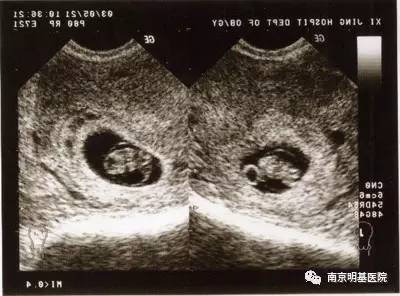

2.孕6周时出现胎心搏动,有胎芽,就像是一颗种子才刚刚发芽一样。